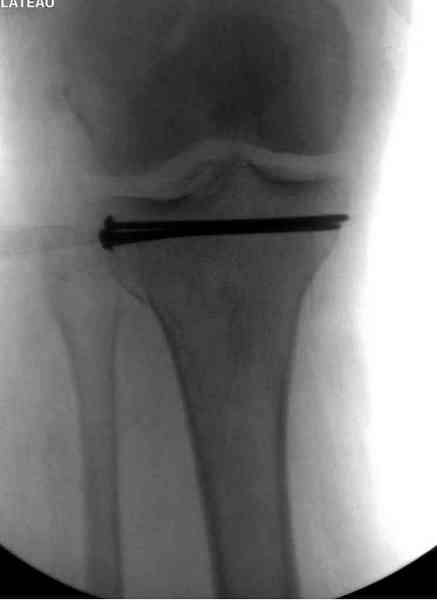

Основная задача в лечении околосуставных переломов является создание солидного базиса в субхондральной зоне. Пластина подпорка (Butress) или субхондральные перкутанные шурупы в виде плота (Raft) для ранних движении.

У больного двухстороннее повреждение, ограничен в нагрузке не менее 8-10 недель. После односторонней фиксации будет активным, хотя бы в пределах койки. Без спешки дождаться улучшения кожных покровов, и аппаратом Илизарова в комбинации с шурупами или спицами, из мини-доступов.